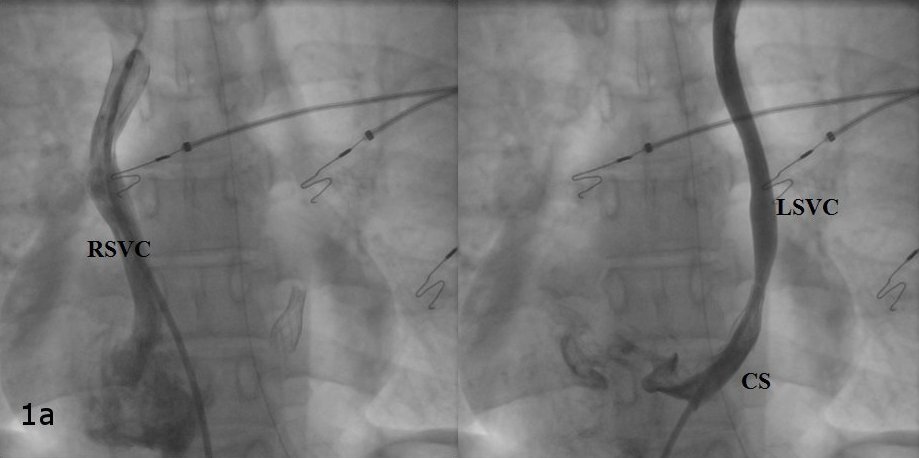

A 19-year-old female underwent repair of complex congenital heart disease (atrial and ventricular septal defect with a criss-cross atrioventricular relationship) in infancy. Because or recurrent palpitations she underwent an electrophysiology study. Atypical atrioventricular nodal reentrant tachycardia was diagnosed. Catheter ablation was performed successfully using cryothermal energy. The diagnostic and therapeutic approach is discussed.